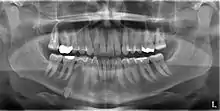

An impacted tooth is one that fails to erupt into the dental arch within the expected developmental window. Because impacted teeth do not erupt, they are retained throughout the individual's lifetime unless extracted or exposed surgically. Teeth may become impacted because of adjacent teeth, dense overlying bone, excessive soft tissue or a genetic abnormality. Most often, the cause of impaction is inadequate arch length and space in which to erupt. That is the total length of the alveolar arch is smaller than the tooth arch (the combined mesiodistal width of each tooth). The wisdom teeth (third molars) are frequently impacted because they are the last teeth to erupt in the oral cavity. Mandibular third molars are more commonly impacted than their maxillary counterparts.

Classifications enable the oral surgeon to determine the difficulty in removal of the impacted tooth. [9] The primary factor determining the difficulty is accessibility, which is determined by adjacent teeth or other structures that impair access or delivery pathway. The majority of classification schemes are based on analysis on a radiograph. The most frequently considered factors are discussed below.

Angulation of tooth

Most commonly used classification system with respect to treatment planning. Depending on the angulation the tooth might be classified as: